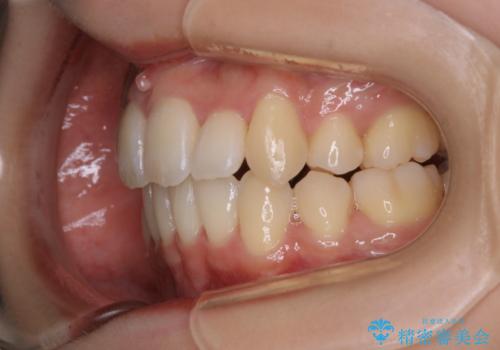

がたつきが強いガチャ歯。埋伏歯抜歯+矯正。すごいところに犬歯が埋まっていたのを抜いてワイヤー矯正治療

- 歯のがたつきを主訴に来院されました。

がたつきの強さから4本抜歯の必要性がありましたが、右上の歯は犬歯が一本埋まっており、乳歯がある状態でした。

右上については先に乳歯を抜歯して、犬歯が使えるようであれば第一小臼歯を抜歯することとして治療を開始しました。